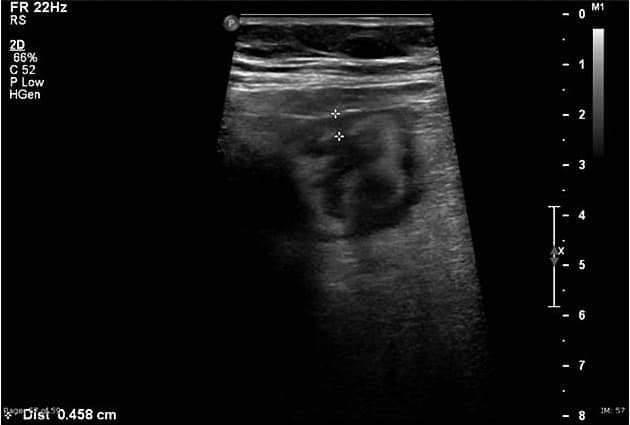

Kết quả Hình ảnh Văn bản: Ruột thừa được đánh giá toàn bộ chiều dài. Nó nằm ở hố chậu phải. Chiều dài của ruột thừa khoảng 90 mm. Phần gần khoảng 40 mm chiều dài của ruột thừa cho thấy đường kính bình thường (< 6 mm), khả năng nén. Phần xa của ruột thừa cho thấy giãn (đường kính > 6 mm), không thể nén, tăng sinh mạch, lòng không giãn với dấu hiệu bảo tồn chữ ký ruột. Không có sỏi phân tại vị trí chuyển tiếp từ ruột thừa giãn đến bình thường. Có viêm mỡ quanh ruột thừa ở phần xa. Manh tràng và hồi tràng tận cùng bình thường.

Ruột thừa được cắt bỏ cho thấy đường kính bình thường của đoạn gần. Phần còn lại của dạ dày thừa bị giãn. Không có thủng thành.